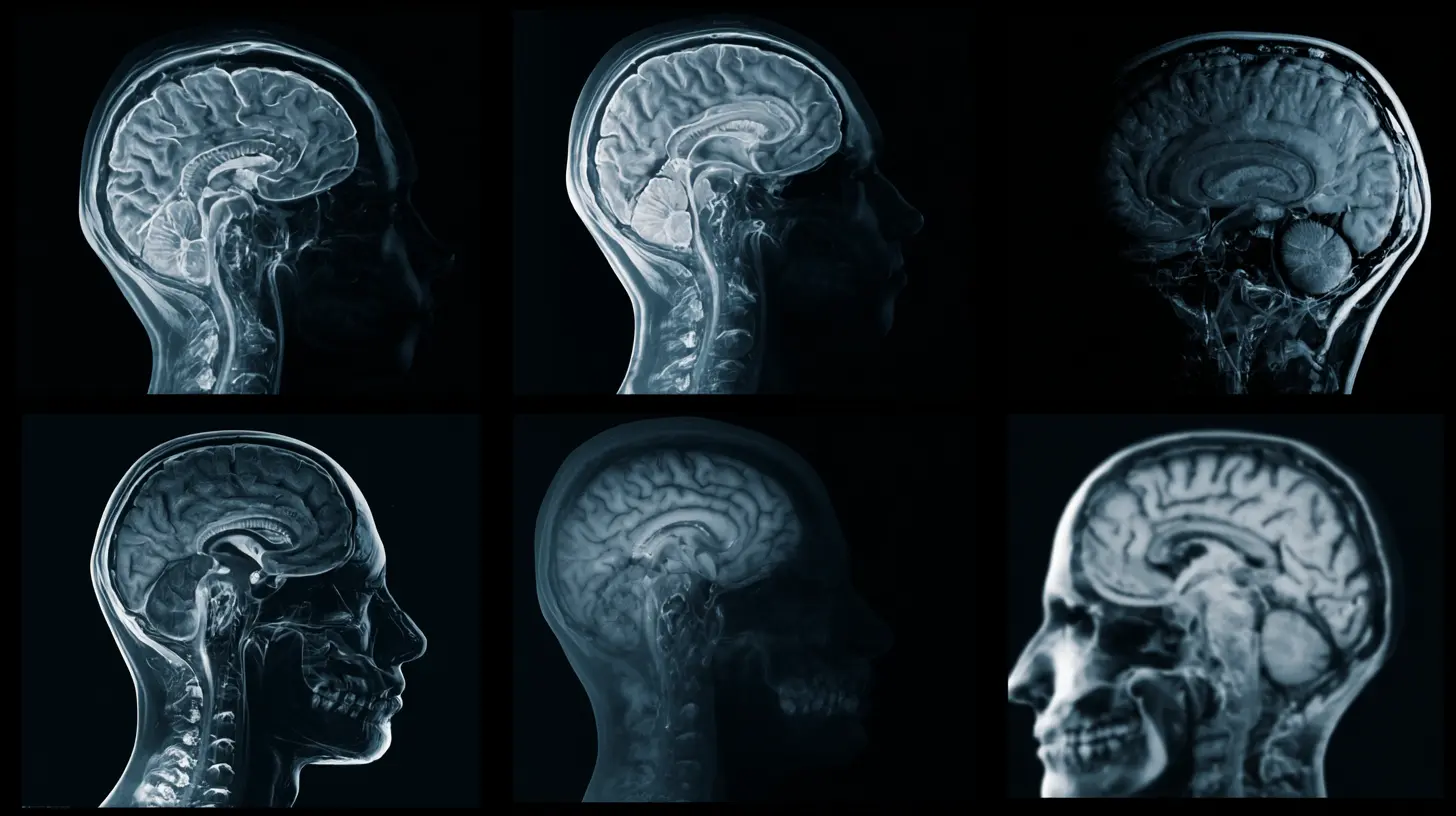

Then came functional magnetic resonance imaging (fMRI) and other neuroimaging techniques. Suddenly, we could watch the brain in action. We could see which neighborhoods lit up when someone felt love, made a risky decision, or recognized a face. It was like astronomers getting the Hubble Telescope after centuries of squinting through handheld lenses. The promise was intoxicating: to finally ground the abstract concepts of psychology—motivation, personality, psychopathology—in the solid, biological reality of blood flow and neural circuits.

The reality, however, will be profoundly significant. Brain scanning, especially when integrated with other data and advanced analytics, will transition from a pure research tool to a powerful clinical and diagnostic aid. It will help us move from treating broad diagnostic categories to understanding individual neurobiological profiles. It will offer probabilities and risks, not certainties and destinies.

Think of it this way: in 2026, a brain scan won’t be a crystal ball that shows your future actions. It will be more like a sophisticated, dynamic map of a unique landscape—your brain. It can show a clinician where the well-trodden paths (neural pathways) are, where the terrain is unstable, and where there might be roadblocks. It can suggest which therapeutic "routes" might be most effective for your particular landscape. But the journey—your choices, your efforts, your life experiences—will still be yours to make.